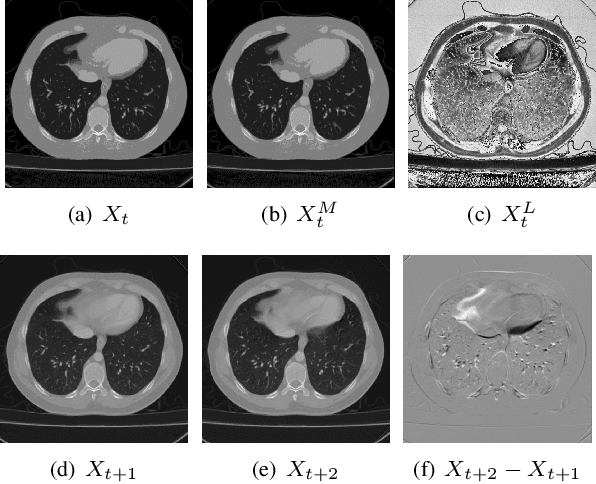

Abstract:Recent advances in learning-based methods have markedly enhanced the capabilities of image compression. However, these methods struggle with high bit-depth volumetric medical images, facing issues such as degraded performance, increased memory demand, and reduced processing speed. To address these challenges, this paper presents the Bit-Division based Lossless Volumetric Image Compression (BD-LVIC) framework, which is tailored for high bit-depth medical volume compression. The BD-LVIC framework skillfully divides the high bit-depth volume into two lower bit-depth segments: the Most Significant Bit-Volume (MSBV) and the Least Significant Bit-Volume (LSBV). The MSBV concentrates on the most significant bits of the volumetric medical image, capturing vital structural details in a compact manner. This reduction in complexity greatly improves compression efficiency using traditional codecs. Conversely, the LSBV deals with the least significant bits, which encapsulate intricate texture details. To compress this detailed information effectively, we introduce an effective learning-based compression model equipped with a Transformer-Based Feature Alignment Module, which exploits both intra-slice and inter-slice redundancies to accurately align features. Subsequently, a Parallel Autoregressive Coding Module merges these features to precisely estimate the probability distribution of the least significant bit-planes. Our extensive testing demonstrates that the BD-LVIC framework not only sets new performance benchmarks across various datasets but also maintains a competitive coding speed, highlighting its significant potential and practical utility in the realm of volumetric medical image compression.